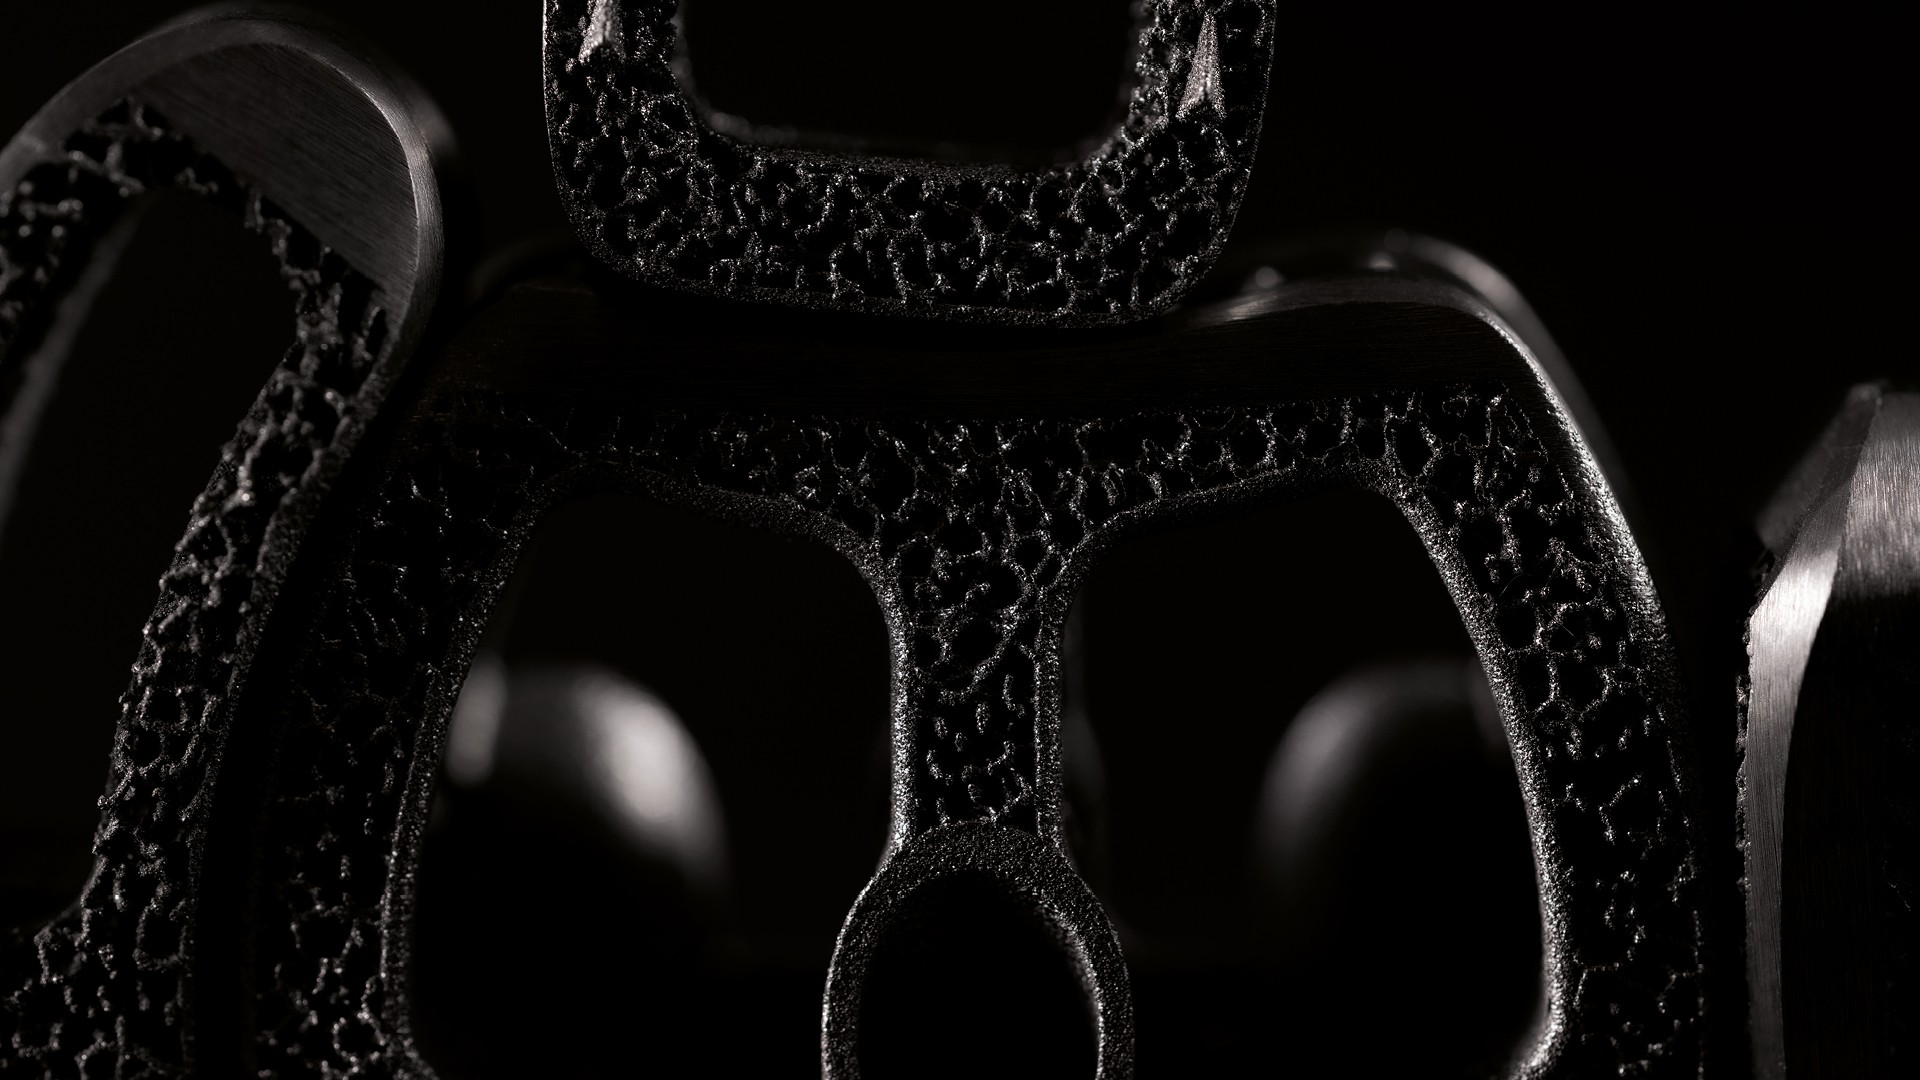

Spineart a développé un algorithme spécifique qui, combiné au procédé classique de fabrication additive, résulte en une matrice exclusive imitant l’os : la Ti-LIFE Technology.

Propulsée par la technologie d’impression 3D et un algorithme spécifique, cette innovation forme une structure unique, semblable à l’os, avec des pores interconnectés conçus pour favoriser la croissance osseuse.

La Ti-LIFE Technology possède une géométrie impossible à réaliser via un procédé de fabrication classique. Le résultat est une structure en titane poreux similaire à l’os trabéculaire naturel; tant en terme de porosité que d’interconnection des pores.

Agissant comme une structure de soutien pour les cellules ostéogéniques (constructrices d’os), la structure poreuse en titane facilite la croissance osseuse à travers et autour de l’implant, garantissant une fusion robuste et fiable.